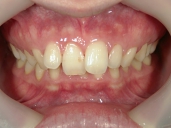

矯正歯科 治療前

矯正歯科 治療前 正面